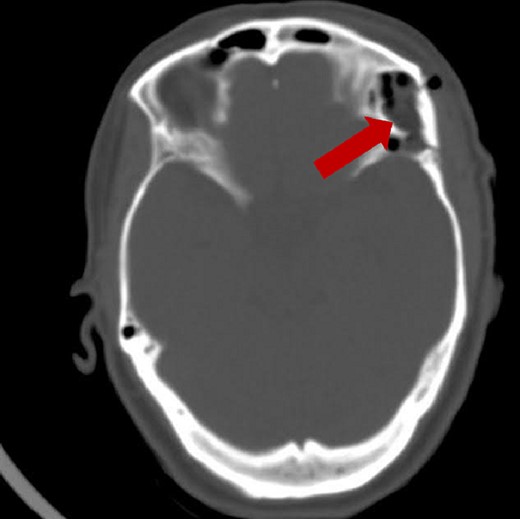

Prior diagnostic imaging included a computed tomography (CT) scan, revealing a hypodense lesion in the left fronto-zygomatic region (Fig. 1). Subsequent brain magnetic resonance imaging (MRI) showed a high-intensity lesion on T1-weighted images (T1WI) (Fig. 2A), and an iso-to-hyperintense lesion on T2-weighted images (T2WI) (Fig. 2B).

Pre-operative axial CT scan displaying a well-defined, low attenuating lesion in the left fronto-zygomatic region.